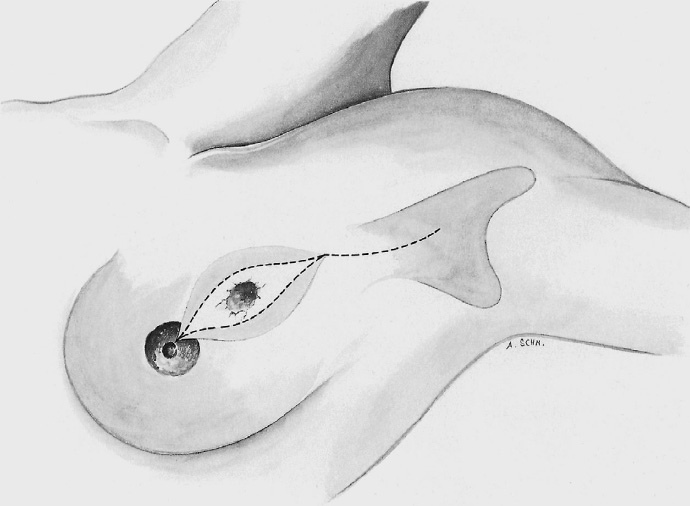

The basic decision on whether to use a complex oncoplastic technique is made when the skin is marked preoperatively, with the patient standing or sitting upright. Many surgeons successfully combine the B-plasty incision with periareolar de-epithelialization and excision of a straight or curved ellipse of peripheral skin (Chapter 1.3). When marking the periareolar deepithelialization pattern, an eccentric incision may be necessary to adjust the repositioning of the nipple–areola complex to the anticipated volume displacement.

The periareolar skin is de-epithelialized. Here, too, there are various options. A strip of the most superficial skin layer can be excised with dissecting scissors applied flat or with a scalpel. It is important not to leave behind any surface containing squamous epithelium, but on the other hand the dermis and the important vascular layer beneath it must not be injured. The purpose of periareolar de-epithelialization is to recenter the nipple–areola complex and also to tailor excess skin to the new breast shape following extensive tumor resection.

To cover the defect, the glandular lobes are mobilized from the adjacent parenchyma after subcutaneous dissection. The principle of intramammary lobe creation is to mobilize large parts of the breast (> 25%) either relative to the skin or relative to the pectoralis muscle. This “liberation” of the breast from one of its two planes of fixation allows adequate dissection and rotation of sufficient breast tissue. The Y-flap and rotation flap shown in Chapter 3.2.1 are examples of intramammary dissection.

The mobilized breast lobes are rotated into the defect and approximated by interrupted sutures. Complete covering of the defect is desirable.

The skin is closed in two layers with recentering of the nipple–areola complex using interrupted sutures (Vicryl 3–0) according to the preoperative de-epithelialization pattern, which can be corrected at this time.